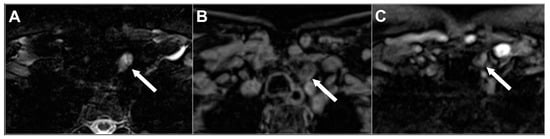

The main characteristic of the hyperplastic and adenomatous parathyroid glands is the high signal intensity on T2-weighted images, usually well visible on fat-suppressed sequences. The appearance could be homogenous or patchy [9], especially when the lesion is larger than 1–1.5 cm, reflecting the presence of hemorrhagic foci, cholesterol clefts, and fibrosis (Figure 5).

Figure 5. Left inferior parathyroid adenoma in 62-year-old woman with pHPT. Fat-suppressed axial T2w (A), pre-contrast axial T1w (B), and arterial frame on dynamic contrast-enhanced imaging (C) acquired on 1.5 T scanner. Parathyroid adenoma (white arrow) appears hyperintense on T2w and hypointense on pre-contrast T1w with heterogenous signal intensity and arterial enhancement due to internal cystic changes. Overall image quality affected by aliasing and motion artifacts.